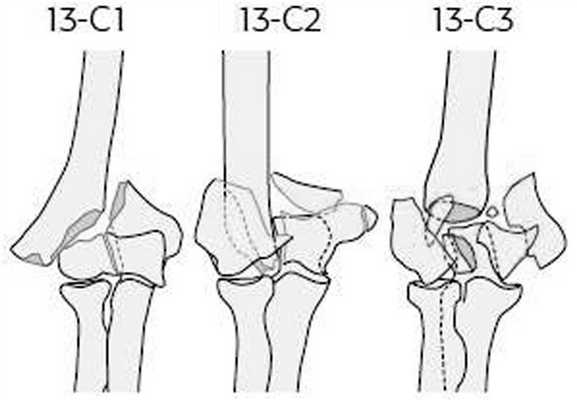

Показаниями к чрескостному остеосинтезу аппаратом внешней фиксации являлись открытые и закрытые оскольчатые внутрисуставные переломы мыщелков плечевой кости типов 13-С1,2,3 по классификации АО [4] (рис. 1). Рисунок 1. Классификация АО внутрисуставных оскольчатых переломов мыщелков плечевой кости (тип 13-С1,2,3). Среди повреждений преобладали открытые и закрытые переломы типов 13-C1,2 по классификации AO. В случае открытых повреждений подобного типа больные были оперированы в течение первых 6 ч с момента поступления. Переломы 13-С1 встречались в 26 (47,2%) наших наблюдениях, переломы 13-С2 - в 20 (36,4%) и переломы 13-С3 - в 9 (16,4%) наблюдениях.